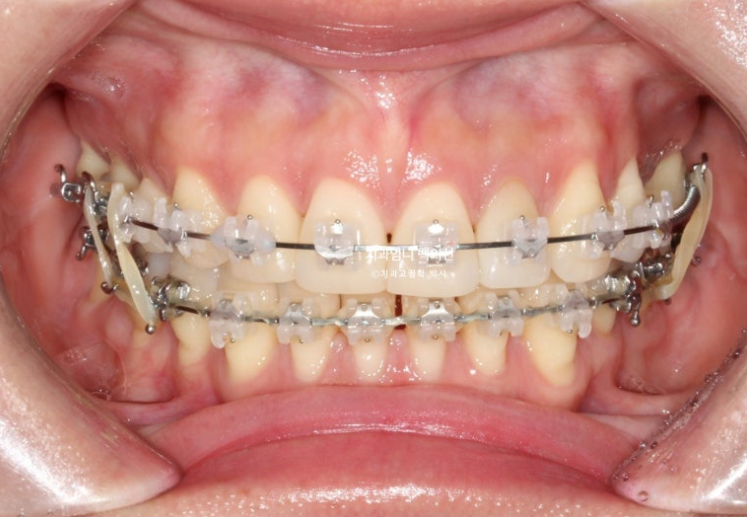

교합 안정화 및 마무리과정을 거쳐 25년 6월 드디어 재교정 치료를 마무리 했습니다.

25.06

총 치료기간은 1년 10개월입니다.

이제 앞니 중심선은 코와 인중과 정확히 맞습니다.

2급이었던 양측 어금니 교합관계는 비로소 1급이 되었습니다.

23.08~25.06

파란 화살표 임플란트가 들어가며 좌우 치아갯수가 맞아졌습니다.

덕분에 중심선도 개선하고 어금니 교합관계도 1급이 되었으며 앞니가 뒤로 쓰러진 옥니도 고칠 수 있었습니다.